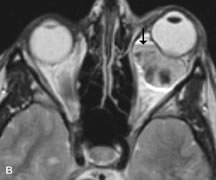

INTRAOCULAR TUMORS

On MRI, uveal melanomas have a typical appearance that helps to differentiate them from other primary and secondary intraocular tumors as well as choroidal detachments. Pigmented melanomas are hyperintense on Tl-weighted images, hypointense on T2-weighted studies, and hyperintense on proton density–weighted examinations (Fig. 24).30,31,50,80–82 These signal characteristics have been attributed to the paramagnetic properties of melanin because of stable free radicals that shorten the T1 and T2 relaxation times. Moderate enhancement is seen on postgadolinium T2-weighted images. Gadolinium-enhanced T1-weighted images are particularly sensitive in detecting choroidal melanomas.83 MRI may be less sensitive in detecting extrascleral extension of tumor than echography performed by an experienced ultrasonographer.84

Fig. 24. A. T1- and (B) T2-weighted MR scans demonstrate a small nodular intraocular mass (arrows) that is very hyperintense on the T1-weighted scan and hypointense on the T2-weighted image. This signal intensity pattern is due to the presence of free radicals within melanin granules. C and D. Postcontrast fat-suppressed T1-weighted scans demonstrate homogeneous intense enhancement of the lesion and no evidence of seleral penetration or optic nerve invasion.